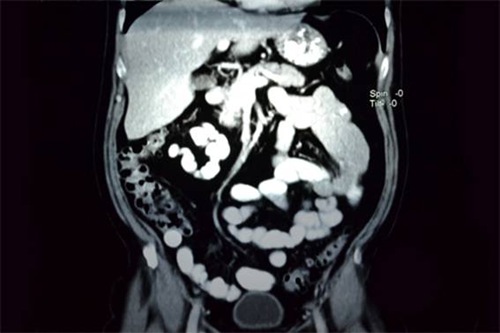

Através de um exame de rotina (colonoscopia), foi verificada a presença de uma neoplasia em determinada área do cólon. Essa neoplasia leva o nome de adenoma, que pode ser de baixo ou de alto grau. Retirado material para exame, ficou constatado que o adenoma era de alto grau, necessitando, então, ser retirado. A cirurgia para extirpar o adenoma chama-se colectomia parcial ou hemicolectomia, que é a remoção parcial (metade ou menos), do intestino grosso (cólon). A colectomia parcial é realizada através de uma grande incisão na parede abdominal. A área afetada do intestino é removida e é efetuada a ligação das duas terminações restantes através de um grampeador que usa grampos de titânio. No meu caso foi retirado um pedaço de 22 cm do intestino grosso e o local da incisão é uma ferida com cerca de 15 cm de extensão na zona abdominal (e o médico havia feito o sinal afastando dois dedos a uma distância de mais ou menos uns 8 cm). O material retirado seguiu para a patologia a fim de verificar se seria ou não de um adenocarcinoma (câncer). Pois bem, estou com 15 pontos bem espaçados num corte vertical na linha do umbigo.